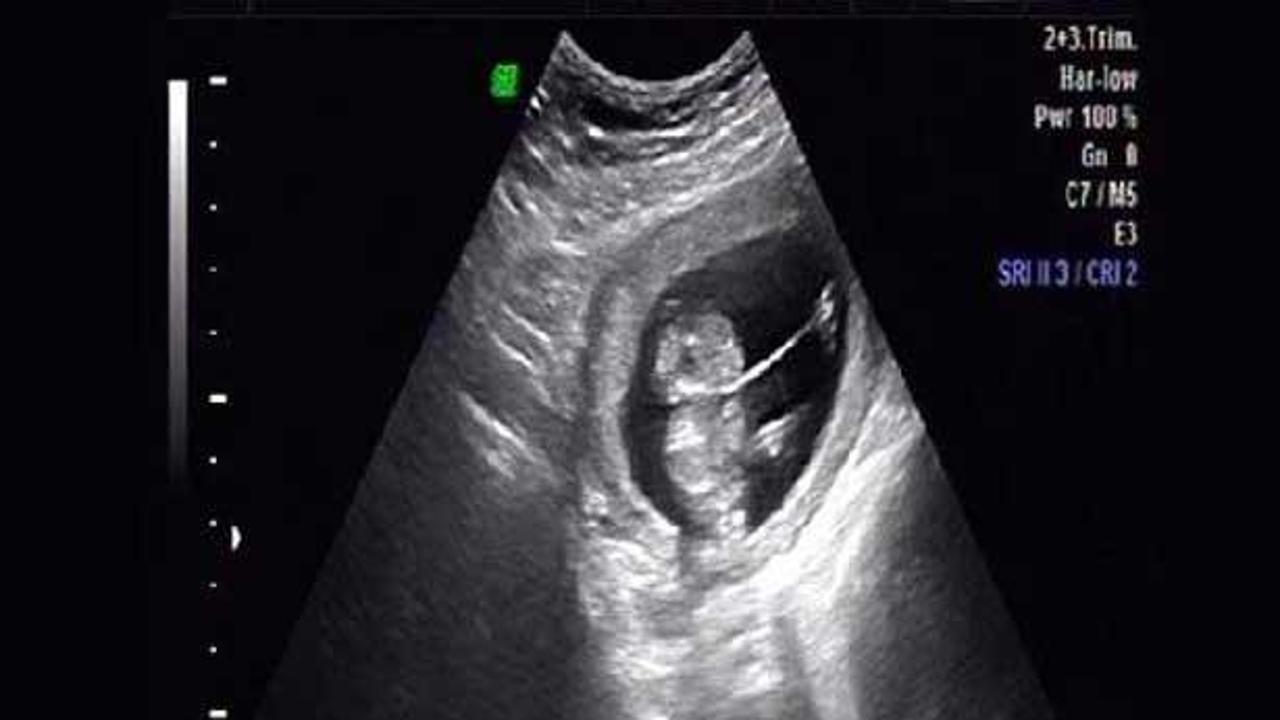

Konya'da, yapılan muayenede dudak ve damak yarığı, parmaklarda şekil bozukluğu, ayak ve kollarda bağ dolanması neden olan 'Amniyotik Band Sendromu' saptanan anne karnındaki 13 haftalık bebek ameliyat edildi.

Bebeğin ayaklarına dolanan 'Amniyotik Band', başarılı bir operasyon sonrası alındı. Ameliyatı gerçekleştiren Özel Medicana Hastanesi Kadın Hastalıkları ve Doğum Uzmanı Prof. Dr. Metin Çapar, 'Amniyotik Band Sendromu'nun 1200 doğumda bir görüldüğünü söyledi. Amniyotik bantın bebeğin içerisinde bulunduğu içi amniyon sıvısı ile dolu amnion zarının katlantı yapması sonucu oluşan ip veya perde benzeri oluşan bir yapı olduğunu kaydeden Prof. Dr. Çapar, şunları söyledi:

"Son olarak 17 haftalık bir bebeğin amniyotik band ameliyatını gerçekleştirmiştik. Ama anne karnındaki 13 haftalık bir bebeğin amniyotik band ameliyatı Türkiye'de ilk kez yaptık. Ameliyatı lokal anesteziyle ultrason altında gerçekleştirdik. Kalın bir aminiyosentez iğnesi ve çok özel ince bir makas kullandık. Amniyoz zarı içerisindeki bu bandı çıkardık. Bu ameliyat sonrası doğacak bebekte oluşma ihtimali bulunan el, kol, ayak veya parmak olmaması, yarık damak ve dudak oluşması gibi deformasyonları engellemiş olduk."